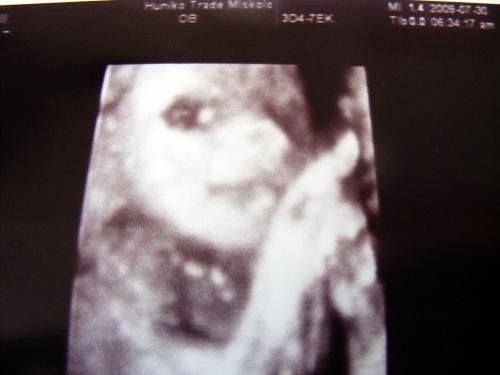

Mi megvagyunk, növögetünk ezerrel. Pénteken voltunk 4d-n, minden rendben van. Lilike most már biztos hogy Lilike, nem szégyenlős a drágám, rendesen bepucsított és szép kis hurija is van. 1000g-nak mérték és azt mondta a doktornő, hogy készüljünk, hogy szép nagy baba lesz. Nem a súlya lesz óriási, hanem szép hosszú lesz, lehet hogy 58-60 cm :lol: Mondjuk erre számítottunk mert mi se vagyunk alacsonyak :lol: Egyébként tiszta apja a kis drága. Nagy csókos szája van és kis kerek arcocskája. Teljesen beleszerettem :lol: Még puszit is küldött nekünk a kis husi szájával. Teszek fel pár képet nektek.

Kis csókos szájú

Vitathatatlan nunis

Nyitott szemmel